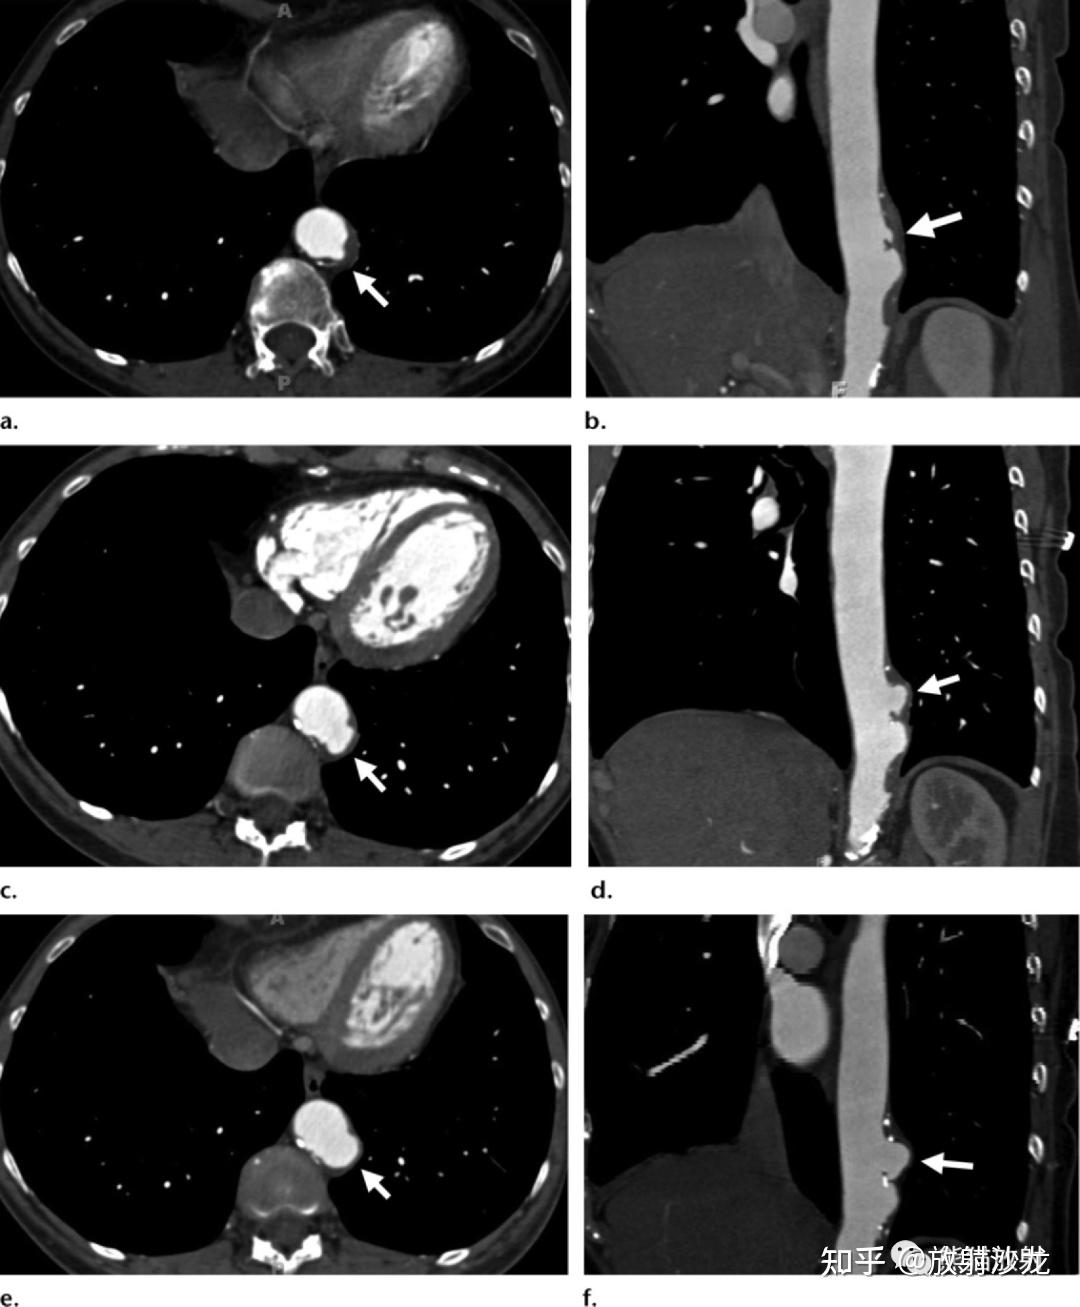

腹主动脉瘤的随访哪些ct征象提示其不稳定性